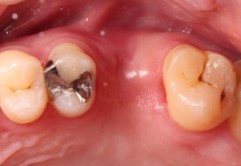

70代 女性

治療前

治療後- リスク・副作用

(薬・注射・レントゲン・ソケットリフト骨造成・サージカルステント・CT・データ分析) - 年齢/性別

- 70代/女性

- 患者の具体的な症状

- 右上56欠損のため義歯を使用していたが不安定で十分噛めないため、インプラント治療を希望

- 検査方法

- コーンビームCT、レントゲン撮影

- 診断結果

- 右上56欠損

- 治療詳細

- 右上56部、コーンビームCTによる画像診断で垂直的な骨高、骨密度の不足のため、ソケットリフトによる骨再生治療とインプラント埋入2本を同時にショートインプラントを用いて行った。

- 通院回数

- 7回

- 治療期間

- 7か月